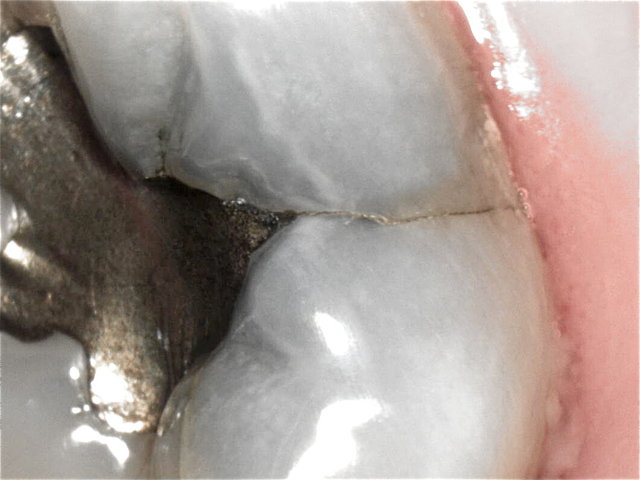

Randspalten in undichter Amalgam-Füllung ...

Composit-Füllung by CLINICDENT ✓